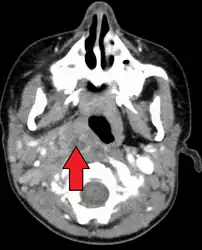

A computed tomography (CT) scan is the definitive diagnostic imaging test.[6]

Large retropharyngeal abscess as seen on CT